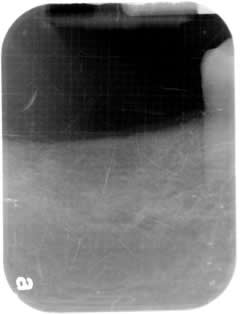

Mental Foraman:

There is an anatomical feature called mental foramen, that where the madibular nerve coming out from the mandible a little bit behind the corner of the mouth.

This is important not to touch this nerve.